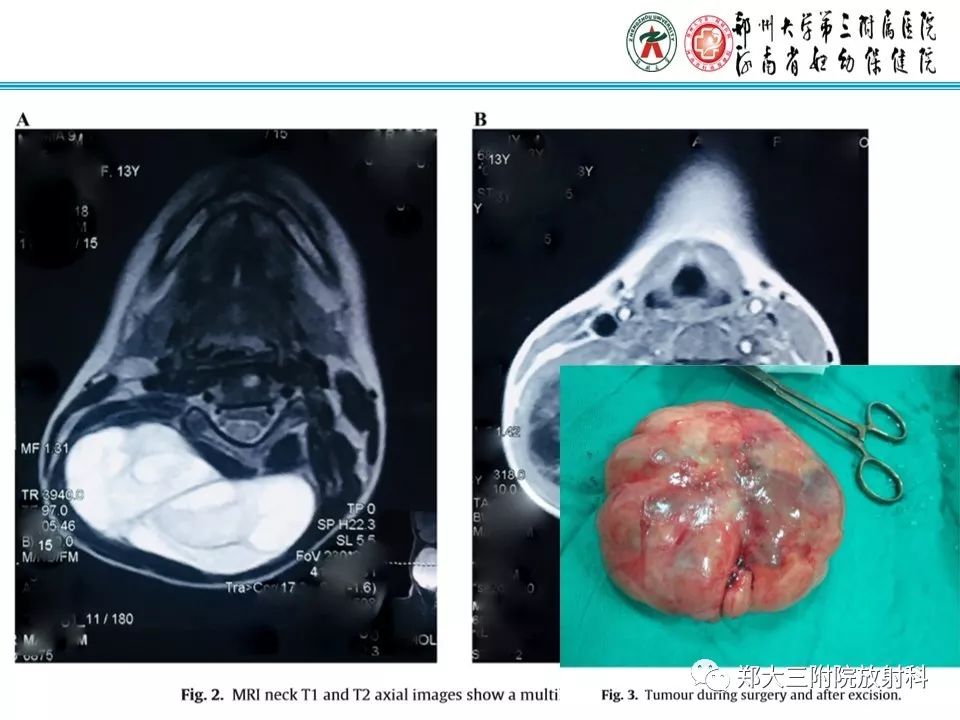

儿童颈部脂肪母细胞瘤1例CT影像诊断

【病例】儿童颈部脂肪母细胞瘤影像诊断